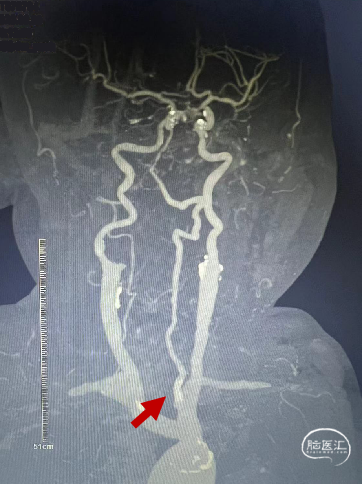

CTA提示:右侧椎动脉纤细,左侧椎动脉V1、V4段纤细。

左侧椎动脉开口重度狭窄,前向血流缓慢,V4闭塞。

左侧椎动脉V4段闭塞、左侧椎动脉起始部重度狭窄、左侧小脑急性脑梗塞、右侧颈内动脉起始部狭窄。